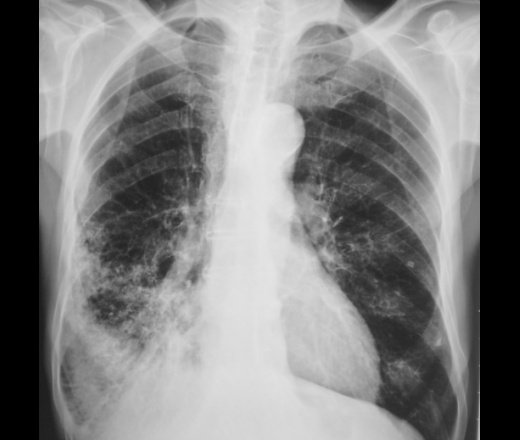

Это конечно шутка, а на самом деле здесь пневмония на фоне порока развития правого легкого. Справа внизу множественные ячейки. Ну и последствия травмы справа. Пневмония, думаю - дело временное.

Типа «сотовое лёгкое»? Нет? интересно, как оно выглядело до болезни?

Томограммы.

Диф Ds поликистоз

бронхоэктазы

пневмосклероз с развитем сотового лёгкого?

Пневмония (возможно грибковая)

Я никак не могу разглядеть просвет среднедолевого бронха, проходим ли он в должной степени? Очень интересно было бы посмотреть контроль